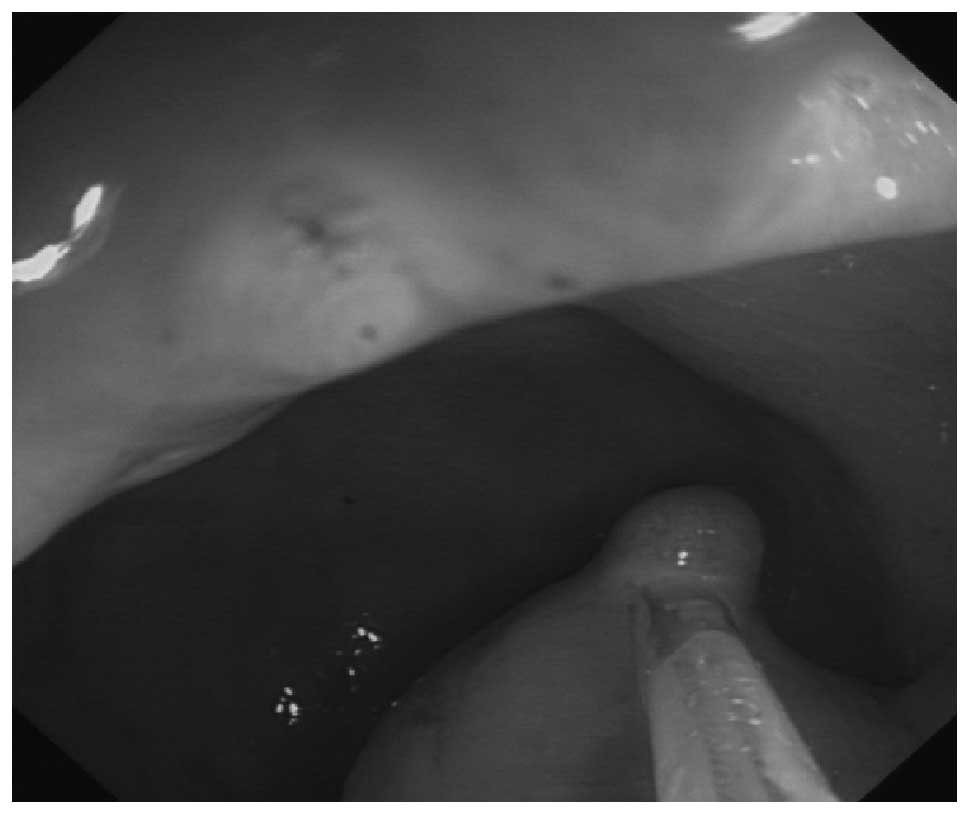

Evaluation of colonoscopy in the diagnosis and treatment of rectal carcinoid tumors with diameter less than 1 cm in 21 patients

The aim of this study was to evaluate colonoscopy in the diagnosis and treatment of rectal carcinoid tumors with diameter <1 cm. Elevated lesions with normal mucosal appearance under colonoscopy were identified. Endoscopic ultrasound (EUS) was performed in 16 patients. Lesions diagnosed as rectal carcinoid tumors were resected by endoscopic mucosal resection (EMR). The diagnosis of specimens by EMR was confirmed by pathological examination. Immunohistochemical staining was undertaken and follow-up data were collected. Twenty-two lesions were found among the 21 cases. The majority of these were located within 10 cm of the anal opening. Twenty two cases with rectal carcinoids were diagnosed by EUS under colonoscopy and all cases were verified by pathological examination. The resection rate was 95.5% (21/22). Of the lesions, six were mucosal and 10 were submucosal. Immunohistochemistry was undertaken for carcinoid tumors. Histological patterns of rectal carcinoids revealed solid nests or trabecular patterns. Eleven cases were synaptophysin (SYN)-positive, 8 cases were neurone-specific enolase (NSE)-positive and 5 cases were chromogranin A (CgA)-positive. Colonoscopy combined with EUS is effective in the diagnosis and determination of small rectal carcinoids. Endoscopic treatment is effective for small-sized tumors. Pathology and immunohistochemistry remain the diagnostic gold standard.